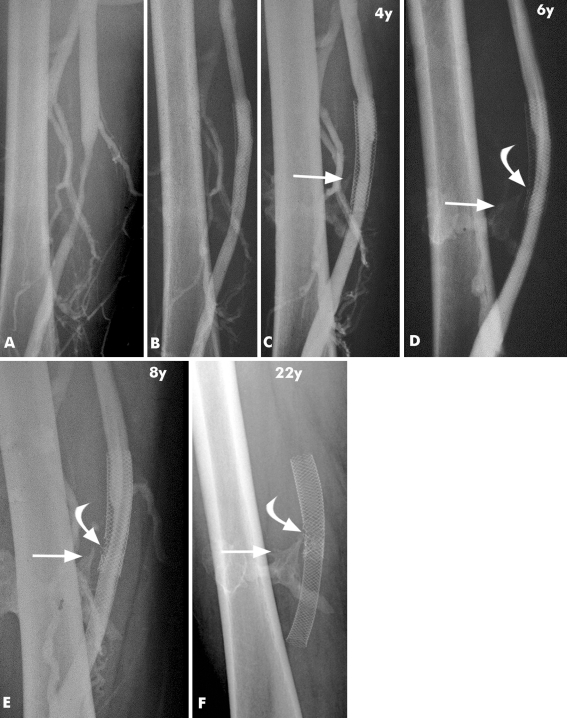

Stent integrity, with normal stent morphology, was documented in 14 of 15 cases (Fig. 1). One stent showed a single stent fracture (patient no. 14). We guess that the reason for this fracture was a calcified hematoma adjacent to the stent, which resulted in chronic mechanical stress (Fig. 2A–F). It is remarkable that even stents placed in the common femoral vein directly over the hip joint (patients no. 1 and 11 through 13) showed no fracture after 83 to 222 months later (Fig. 3A, B).

Fig. 2.

Serial venograms during a follow-up period of 22 years (patient no. 14) after a stab wound injury of the right superficial femoral vein, which was treated with a venous interposition graft, resulting in stenosis of the femoral vein. A Venogram shows severe stenosis corresponding to the venous interposition graft. B Venogram taken after placement of two 14 × 70-mm Wallstents in the superficial femoral vein. C Venogram taken 4 years later shows new soft-tissue calcification adjacent to the patent stent (arrow), which was interpreted as a calcified hematoma or myositis ossificans. The stent is intact at follow-up of 6, 8, and 22 years. D, F A stent fracture can be noticed (curved arrow), which remained mostly unchanged over the years, with no signs of flow impairment or clinical signs of leg swelling. The likely cause of the stent fracture can be identified as the pointed part of the calcification (arrow) interfering with the stent